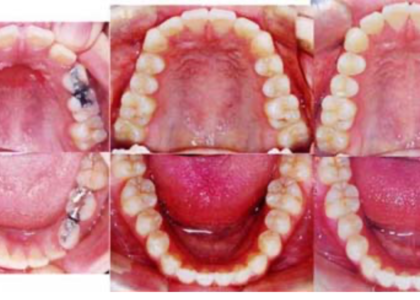

上顎前歯部に叢生(デコボコ)を伴う反対咬合・下顎前突症成人症例

画像説明 : WA ①主訴 : 受け口 ②診断名あるいは主な症状 : 上顎前歯部に叢生(デコボコ)を…